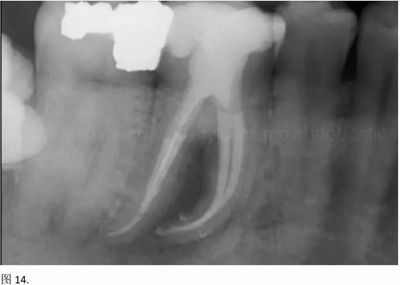

本文的目的是描述一種旨在優(yōu)化根管根尖部分預(yù)備的預(yù)敞技術(shù)。根管頸部或冠方的早期預(yù)敞對于減少初尖銼直徑和根尖部根管直徑之間的差異至關(guān)重要。大量研究表明,手用或機用器械預(yù)敞根管能顯著減少器械折斷的發(fā)生率。